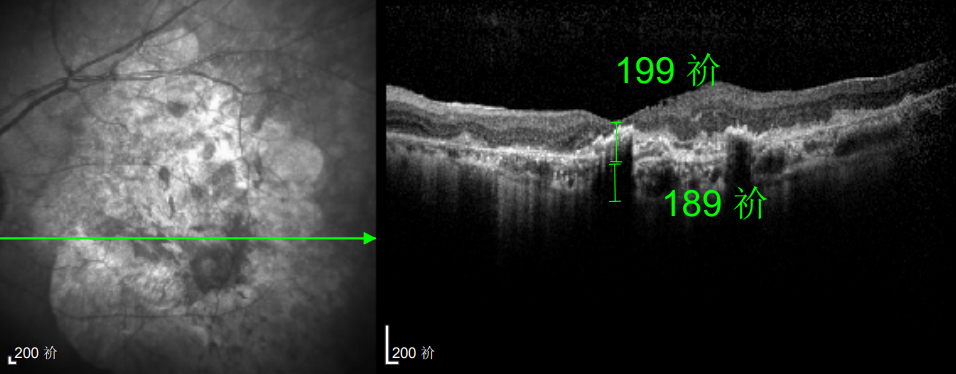

△規(guī)劃化治療后的左眼